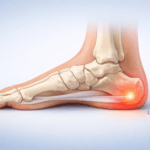

La bursite du pied est une inflammation d’une petite poche remplie de liquide, appelée bourse séreuse, qui joue un rôle d’amortisseur et de protection entre les tendons, les muscles et les os. Quand cette bourse s’enflamme, elle provoque une douleur localisée qui peut devenir handicapante au quotidien.

Bursite rétro-calcaneenne et tendon d’Achille

Située à l’arrière du talon, cette bursite est souvent liée aux frottements avec la chaussure ou aux tensions du tendon d’Achille. Elle provoque une douleur à l’arrière du pied, surtout en marchant ou en montant les escaliers.